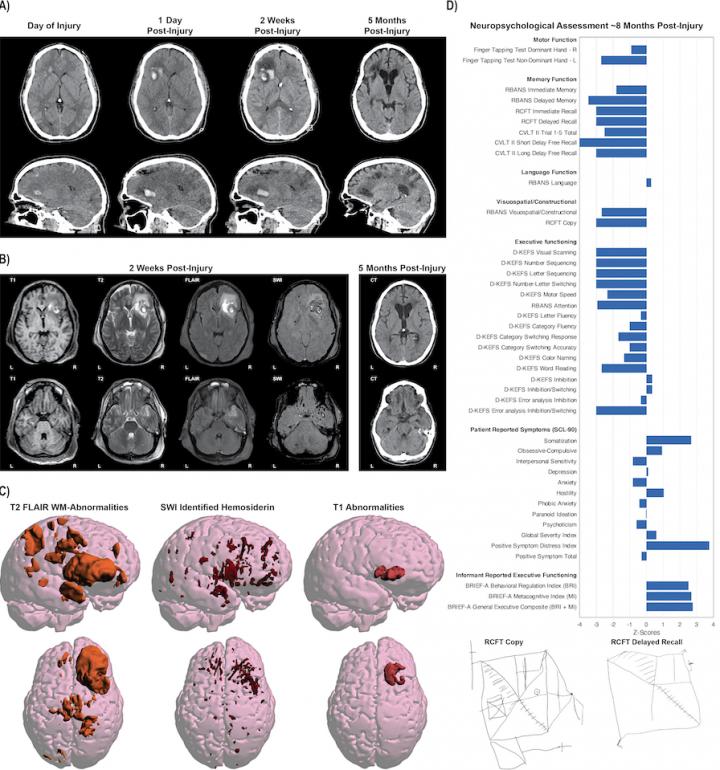

image: This illustration show the complexity of the data obtained from one single patient with moderate/severe traumatic brain injury. Different imaging approaches and techniques have their own unique sensitivity in assessing different aspects of neuroanatomy and neuropathology. What can be seen on images also changes with time since injury. Data from comprehensive clinical and functional assessments using a range of other tools is also important for evaluating patient outcome. Through data harmonization and large-scale analyses of data combined across multiple research sites, the ENIGMA Brain Injury will develop and test methods and procedures for making sense of the complexity in this data

Olsen et al., Brain Imaging and Behavior, 2020